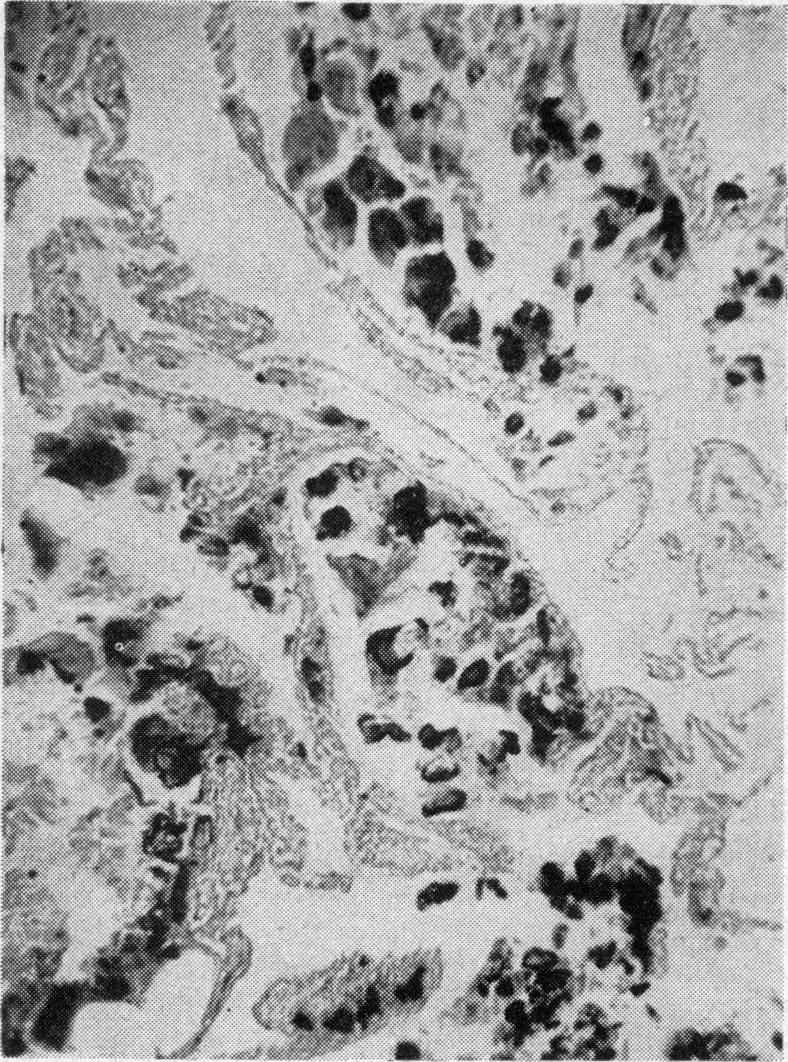

KARLISH A J

Proc R Soc Med. 1962 Mar;55(3):223-5. doi: 10.1177/003591576205500310.